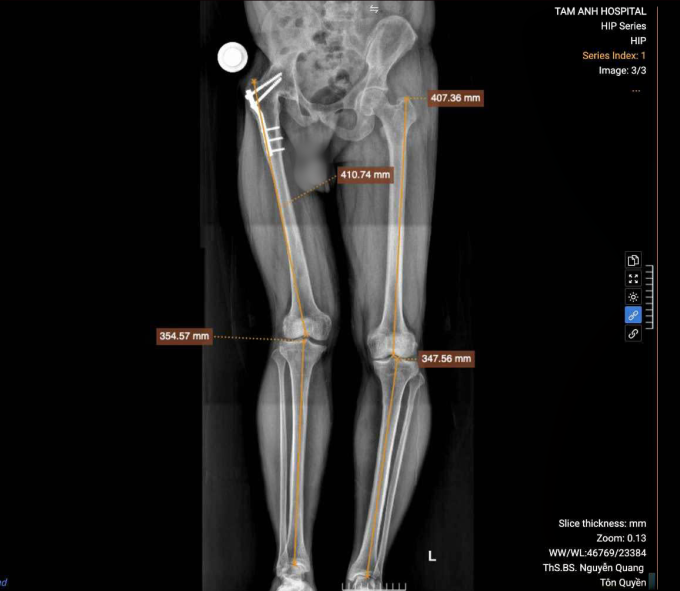

Anh Giang đến Bệnh viện Đa khoa Tâm Anh Hà Nội mong muốn phẫu thuật thay khớp háng để phục hồi vận động. ThS.BS Nguyễn Quang Tôn Quyền, Phó trưởng khoa Chấn thương chỉnh hình, cho biết khớp háng của người bệnh bị đóng cứng hoàn toàn trong tư thế duỗi, sẹo mổ cũ chằng chịt và teo các cơ quanh vùng mông. Kết quả X-quang cho thấy khớp háng khung chậu và cột sống biến dạng nghiêm trọng, gây lệch chiều dài chi khoảng 3 cm.

Khớp háng phải của anh Giang bị đóng cứng khiến chân, khung chậu và cột sống biến dạng sau 32 năm. Ảnh: Bệnh viện Đa khoa Tâm Anh

Bác sĩ sử dụng phần mềm chuyên dụng để đo đạc chi tiết cấu trúc xương của người bệnh, lên các phương án giải phóng khớp, tạo hình lại ổ cối và đặt khớp nhân tạo tại vị trí tối ưu, khôi phục tối đa chức năng vận động trong ngưỡng an toàn cho phép. Một trong những quyết định khó khăn nhất là phải tính toán để chọn cấu phần khớp nhân tạo phù hợp nhất với cấu trúc xương của bệnh nhân, đồng thời phải là loại khớp được bảo hiểm y tế chi trả để giảm gánh nặng chi phí cho người bệnh.